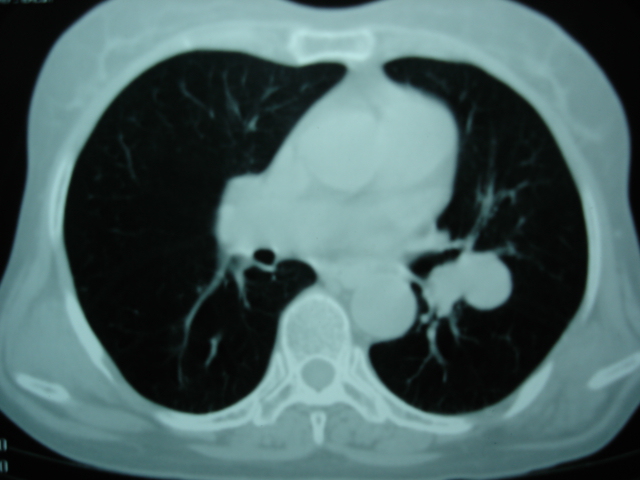

以下是引用卜一在2009-9-7 19:51:00的发言:[br][br] 1 左侧胸内甲状腺占位-多考虑甲状腺腺瘤! 2、左肺门占位-建议增强扫描以便明确性质。 3 慢支并感染! [br]

以下是引用shibing在2009-9-7 20:40:00的发言:[br]左侧胸内甲状腺占位-多考虑甲状腺腺瘤! 2、左肺门占位-建议增强扫描以便明确性质。 3 慢支并感染! [br]